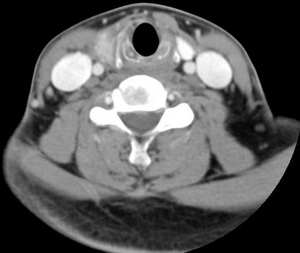

男,25岁,体温39.3度,发现右侧颈部包块.

右侧甲状腺内边界不甚清楚之占位,增强强化不很明显,无钙化。考虑腺瘤,建议活检,除外ca。

肿块还是有强化的,会不会是甲状腺癌呢?但是体温39.3度不好解释,等待高手发言

右侧甲状腺内边界不甚清楚之占位,增强后呈轻度强化。

1.考滤炎性病变可能性大;2.不除外ca。

此病例特点:1、年轻男性,基本上是高热;2、右侧甲状腺肿大呈边界不清之低密度,但甲状腺境界清晰;3、基本没有增强但低密度的周边略呈边缘增强反应;4、最好补充病史:痛否?时间?(如痛、急性起病。)

据此,以甲状腺急性炎症可能性大。

甲状腺脓肿